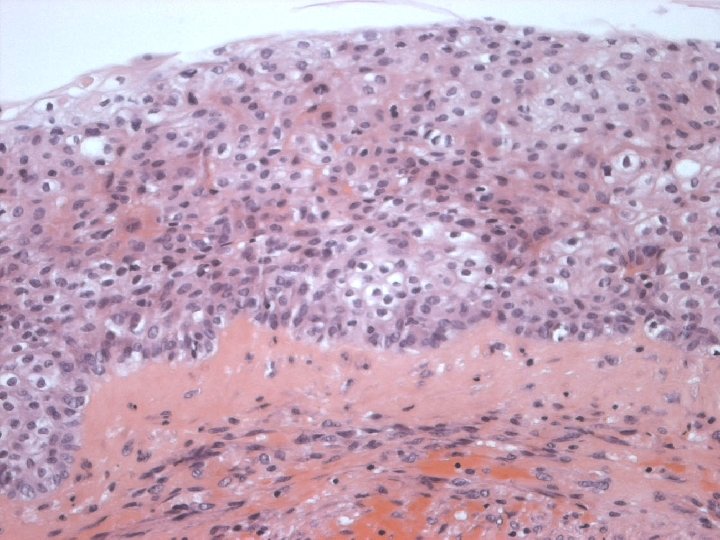

Micro n Similar to SCC at other sites n Cytoplasmic clearing in some

Micro The strongest evidence of a primary SCC of breast is presence of in-situ squamous carcinoma in duct or cyst lining.

Variants of SCC of breast Keratinizing n Spindle cell n Acantholytic n

Immunoprofile-SCC n POSITIVE: – Broad spectrum and high molecular weight cytokeratin( CK 5, CK 34ßE 12) n NEGATIVE: – Vascular endothelial markers – ER – PR